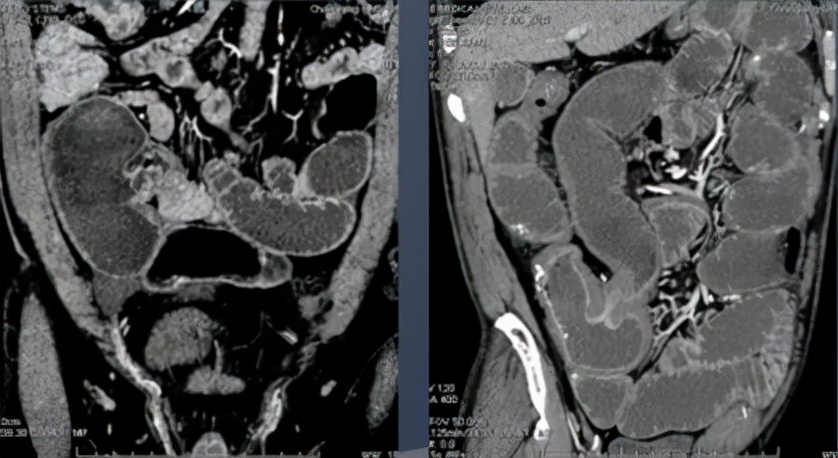

3. CT肠道显像(CTE) 病变在回盲部附近; 节段性改变——不如克罗恩病明显, 腹腔淋巴结——中央坏死或钙化。